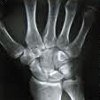

Рентгенография лучезапястного сустава

Рентгенография лучезапястного сустава. Рентгенологическое исследование, показанием к которому в травматологии является подозрение на переломы и переломы дистальной части лучевой и локтевой костей, переломы, вывихи и переломы костей запястья. В других областях медицины метод используется при нарушениях развития, дегенеративно-дистрофических изменениях, гнойных и опухолевых процессах. Процедура не требует подготовки, ее можно проводить амбулаторно или в больнице. В период беременности и в детском возрасте рекомендуется заменить рентгенографию лучезапястного сустава альтернативными методами из-за высокой радиационной нагрузки.

Рентгенограммы запястья в травматологии обозначают подозрение на перелом лучевой кости в типичном месте, перелом Галеацци (перелом дистального радиуса в сочетании с вывихом головки локтевой кости), стилоид перелома и лучевой кости локтевой кости, переломовичихи, искажения и переломы перелома кости запястья. Показаниями к обучению в ортопедии являются артрозы и пороки развития. В ревматологии методика используется для оценки состояния суставов при ревматоидном артрите и ряде других заболеваний. В гнойной хирургии процедура применяется при артрите лучезапястного сустава, в онкологии, при подозрении на доброкачественные и злокачественные новообразования в этой области.